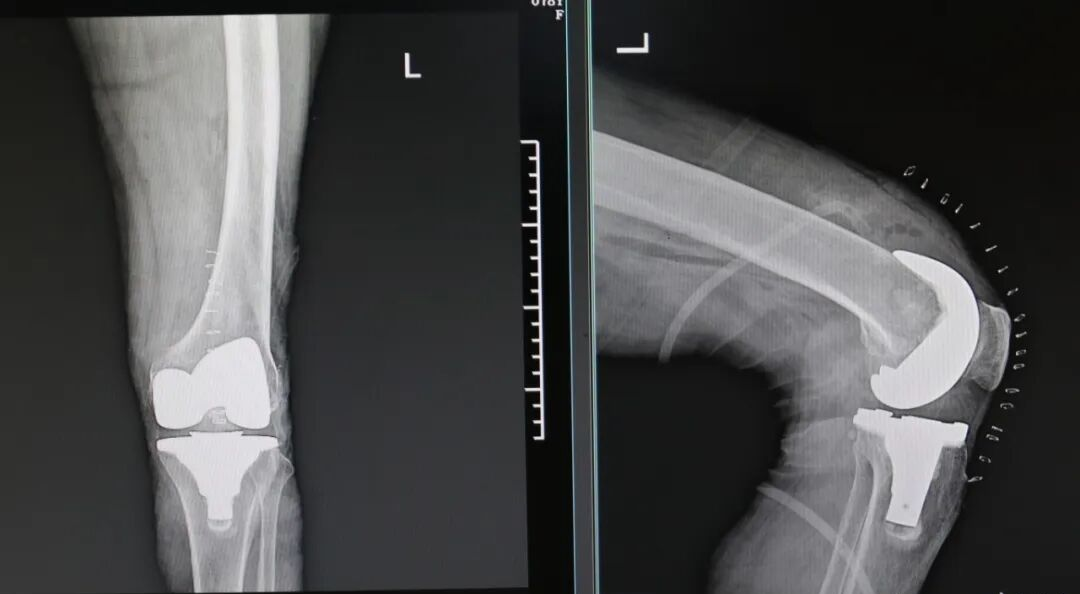

膝盖为啥一凉就“摆烂” 脆皮预警:膝盖,作为全身最复杂、承重最大的关节之一,其实是个“皮薄馅大”的结构。表面肌肉脂肪覆盖少,对温度变化极其敏感。当冷空气来袭关节周围的血管会条件反射般收缩,导致血液循环速度减缓。血流一慢,关节滑液(天然的润滑剂)分泌减少,运走代谢废物(如炎性因子)的速度就变慢。同时,关节内的滑膜和神经末梢对寒冷刺激异常敏感,僵硬、酸胀和疼痛感就会被放大。 疼痛不一定是风湿、类风湿 风湿背锅:“我这是不是风湿?”几乎是所有膝盖受凉疼痛者的第一疑问。医学上的风湿免疫性疾病,如类风湿关节炎、强直性脊柱炎等,是自身免疫系统攻击自身组织导致的严重疾病,必须有明确的免疫指标异常和关节破坏证据。 刘主任表示:“父母说的“老寒腿”或“风湿”,在医生眼里,更准确的描述是“膝关节退行性变”或“骨关节炎”的早期表现,属于关节的磨损、老化,和免疫系统紊乱无关。”下次膝盖疼,别再简单归咎于“风湿”了。分清这一点,才能从盲目的担忧,转向正确的保养和就医方向。 什么才是真“风湿” 危险信号:既然普通受凉疼不是真风湿,那什么症状才需要拉响警报,是真正的风湿病呢?记住以下几个关键词: 对称性疼痛 真正的风湿性关节炎(如类风湿)很少只盯着一个膝盖不放。它通常对称性地侵犯双手腕、手指关节、脚趾等小关节。如果你的疼痛是“双膝+双手”组合,就要警惕。 晨僵 早上起床后,关节僵硬得像生了锈,活动超过30分钟甚至1小时才能缓解,这是典型的炎症性“晨僵”,是风湿病的重要标志。单纯受凉的酸痛,活动几下反而会好转。 全身性不适 身体会发出其他信号:不明原因的长期低热、乏力、体重下降,或者出现皮疹(如脸颊蝶形红斑)、反复口腔溃疡、口干眼干、脱发等。 休息的时候也痛 关节在静止、休息时疼痛更明显,适当活动后减轻,这与劳损性疼痛(活动后加重)相反。 如果“膝盖疼”仅仅是受凉诱发、保暖缓解、位置固定、没有全身症状,那么它属于劳损或退变的范畴远大于风湿病。了解这些区别,能避免不必要的焦虑。 什么时候需要找医生 疼痛性质改变:从“受凉才疼”变成持续疼、夜间静息痛。 功能出现障碍:膝盖突然卡住动不了、打软腿差点跪下,或关节明显肿胀、发热、变形。 居家养护无效:严格保暖休息超过1周,疼痛毫无缓解。 近期一位60多岁的老人,他就是典型的风湿关节炎,膝盖遇冷就疼,起初没当回事,就是贴敷膏药,十多年就这样间歇疼,最近一年疼痛明显加剧,上下楼梯困难,尤其是早上起床后麻木僵硬,这才让孩子们带着来到我院。 刘海亮主任仔细为老人检查,发现他已是终末期风湿性关节炎,保守治疗已经起不到任何效果,针对这类情况,通常考虑进行膝关节置换手术,可有效解决膝关节磨损、矫正变形,并消除患者的疼痛。 完善术前准备,老人的膝关节置换手术成功完成,老人的新生活也即将开始。 术后第二天老人即可下地,及时有效的康复锻炼可以达到快速康复的效果。